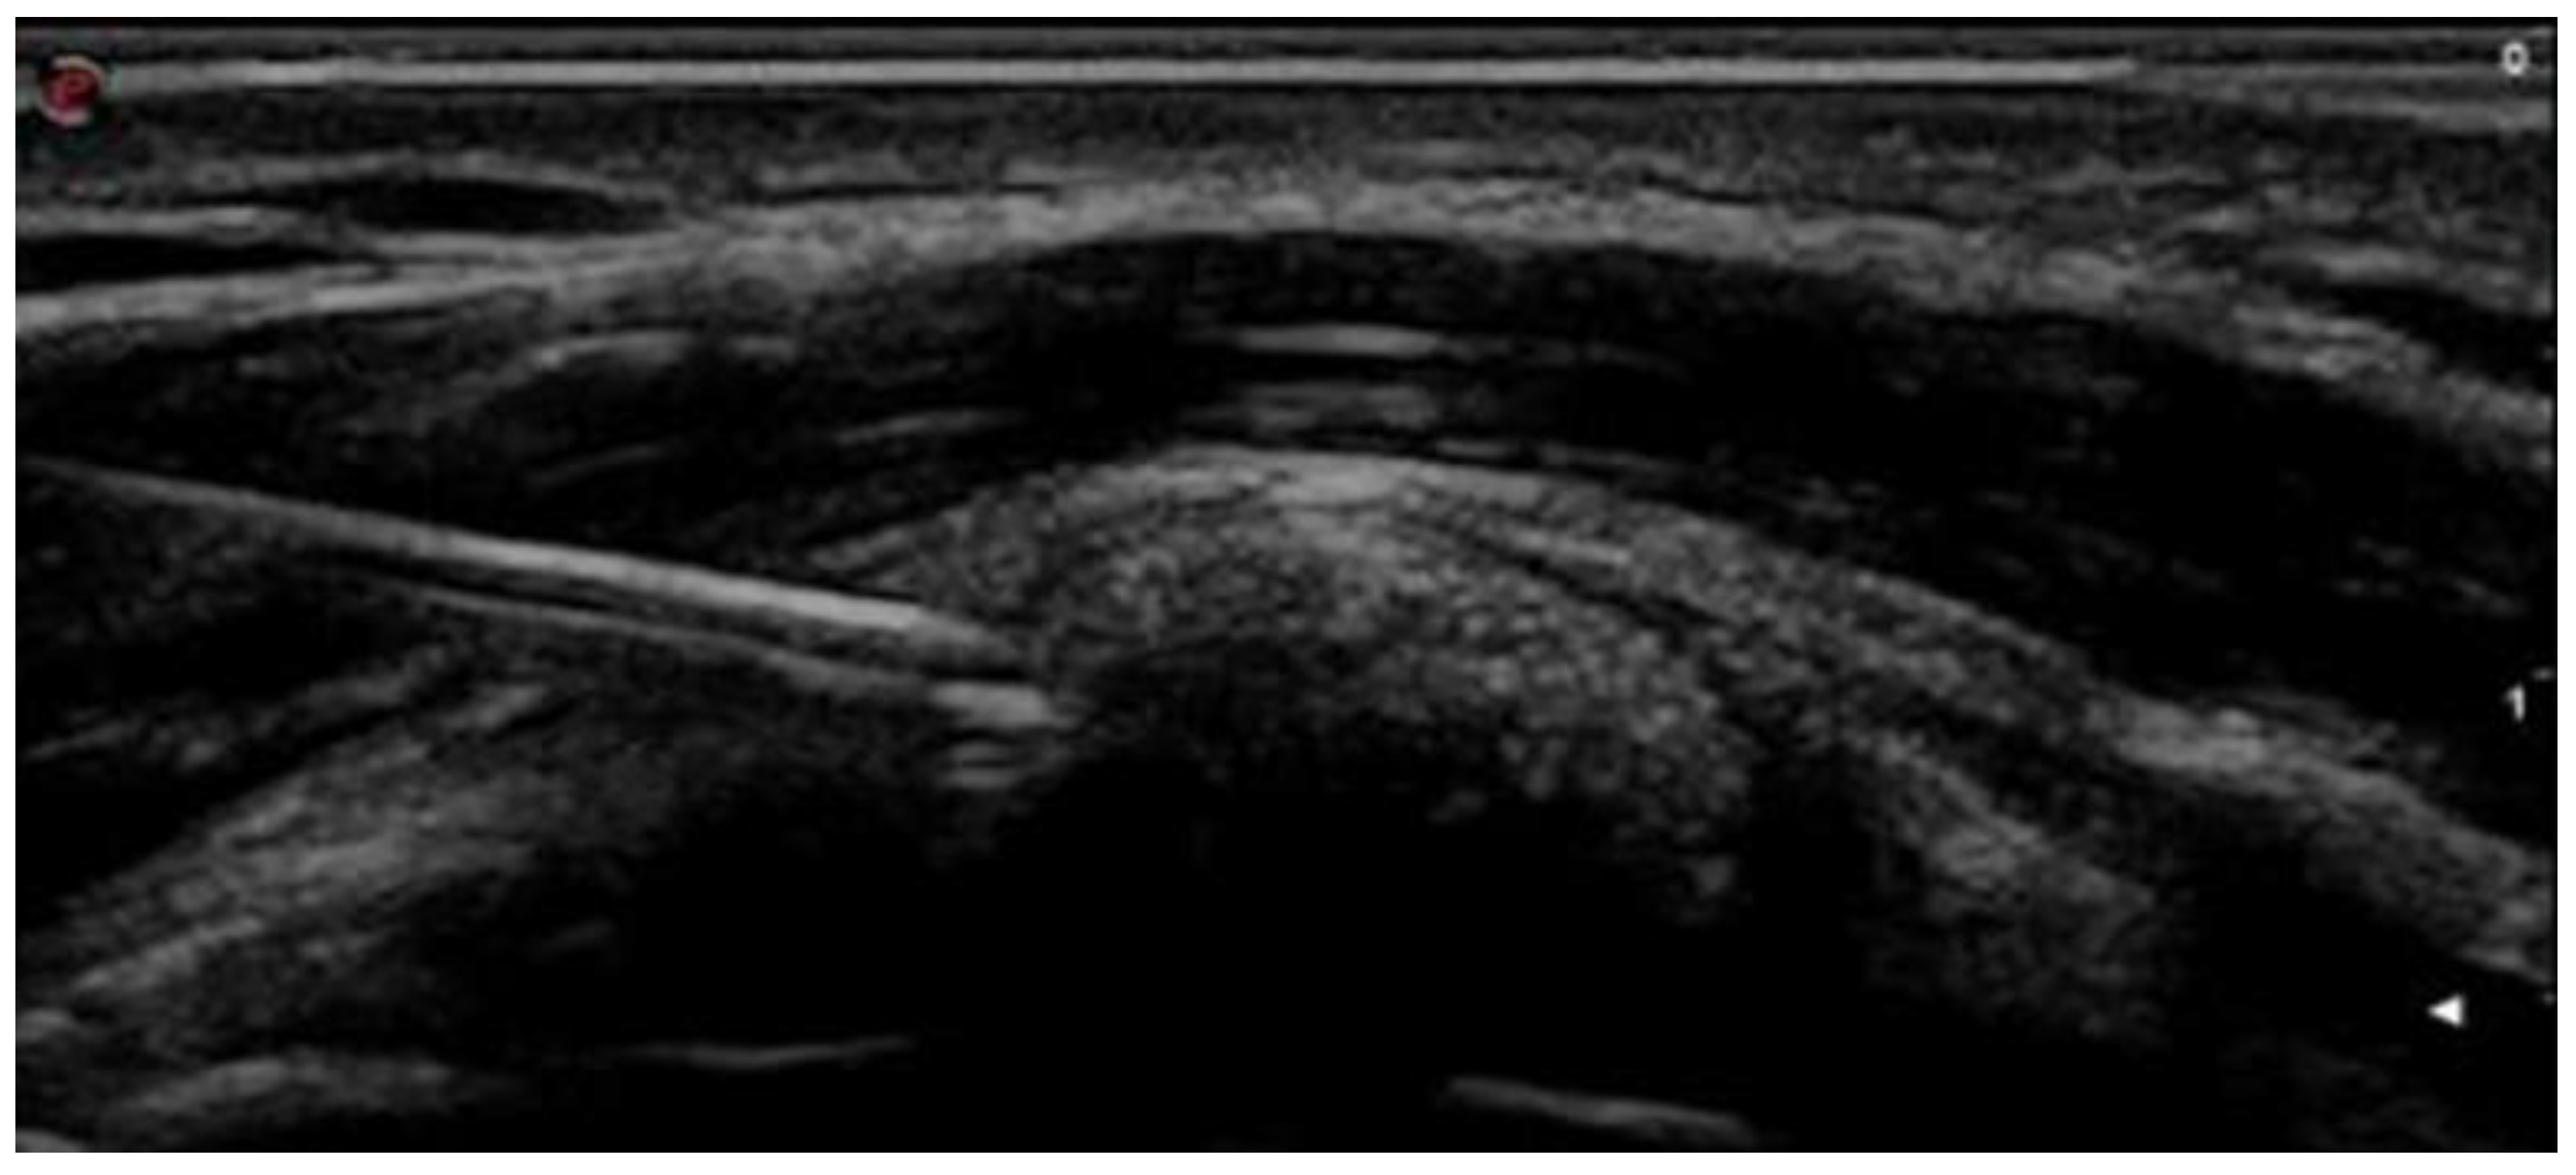

2.2. Intervention

- Sconfienza, L.M.; Viganò, S.; Martini, C.; Aliprandi, A.; Randelli, P.; Serafini, G.; Sardanelli, F. Double-Needle Ultrasound-Guided Percutaneous Treatment of Rotator Cuff Calcific Tendinitis: Tips & Tricks. Skelet. Radiol. 2013, 42, 19–24. [Google Scholar] [CrossRef]